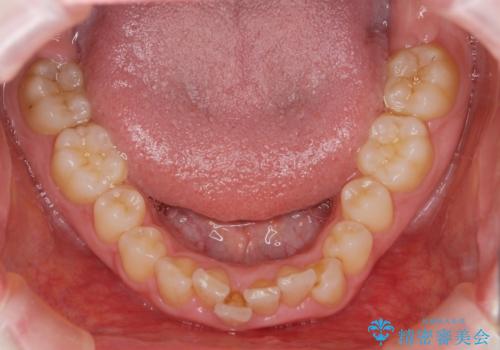

前歯のがたつき 深い噛み合わせを改善したい

- 「前歯のガタつきをきれいにしたい、噛んだ時に下の前歯が見えないことを改善したい」とマウスピース矯正を希望され来院されました。

マウスピースに加え、矯正用マイクロインプラントやゴムを併用し、がたつきや噛み合わせの深さを改善していきます。

ゴムかけやマウスピースの装用時間、しっかりとマウスピースをはめ込むチューウィーをしっかりと使用したことで良好な治療結果を得ることができました。